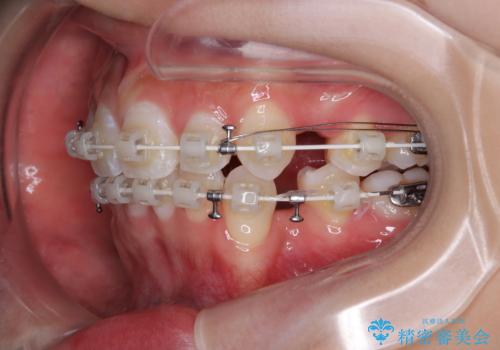

- 矯正装置

- 審美装置

- 2年

- 10-30回

下顎はデコボコが気になっていたため、上下左右第一小臼歯4本を抜去して、ワイヤー装置にて口元の突出感を改善するよう矯正治療を行うこととしました。